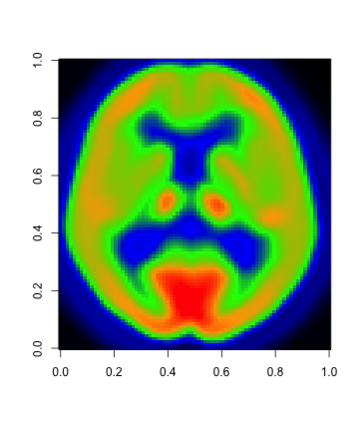

In this paper, we propose a robust estimator for the location function from multi-dimensional functional data. The proposed estimators are based on the deep neural networks with ReLU activation function. At the meanwhile, the estimators are less susceptible to outlying observations and model-misspecification. For any multi-dimensional functional data, we provide the uniform convergence rates for the proposed robust deep neural networks estimators. Simulation studies illustrate the competitive performance of the robust deep neural network estimators on regular data and their superior performance on data that contain anomalies. The proposed method is also applied to analyze 2D and 3D images of patients with Alzheimer's disease obtained from the Alzheimer Disease Neuroimaging Initiative database.